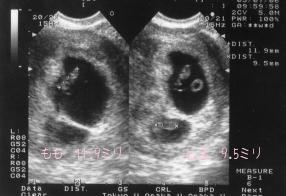

7月 6日7W3D やっととまの心臓が動いているのがわかりました。見えにくいですが下の小さな袋の中にいます。